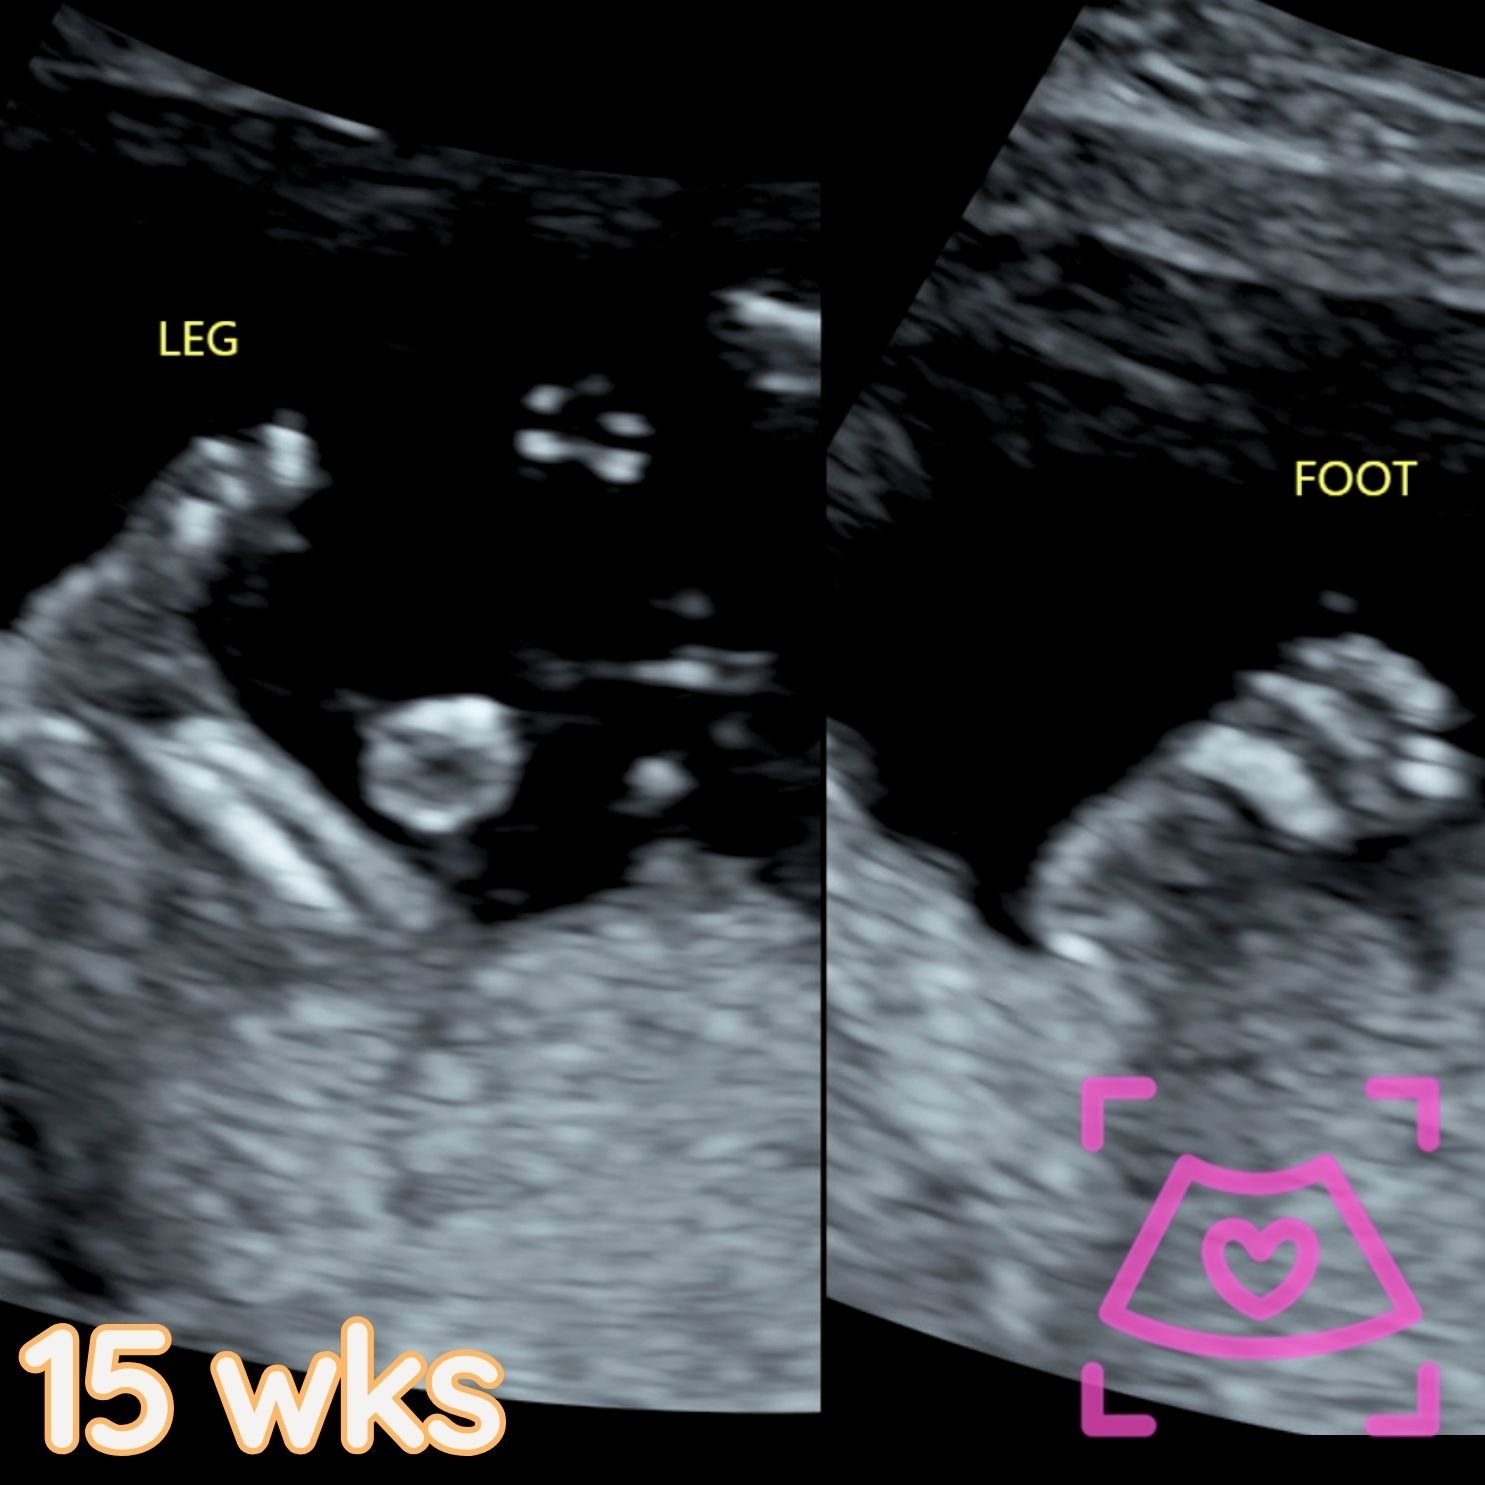

All ultrasounds at this facility are performed abdominally (on top). See examples below from 5-40 weeks! Recommended times can be found on the Services Page and when booking.

2nd Trimester